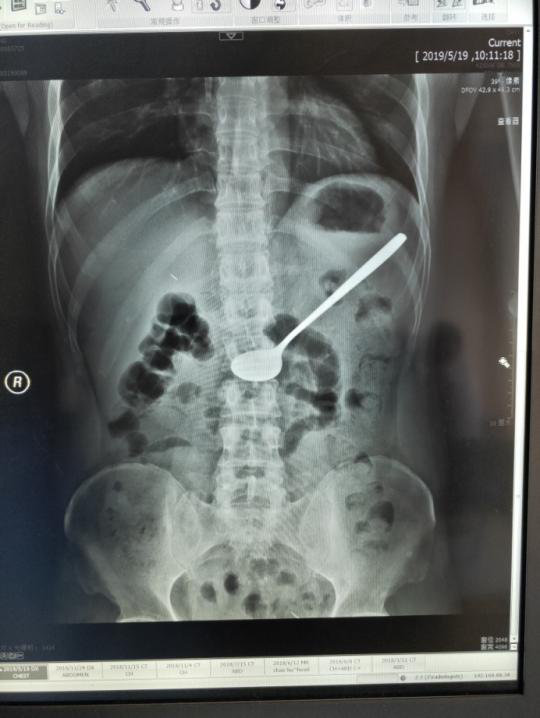

5月19日上午,安医大附属巢湖医院消化内科主任(兼内镜中心主任)李仁君在胃镜室成功为一名患者进行了高难度的胃镜下取异物术,取出了患者吞下的20cm的铁勺。

5月19日上午,像往常一样,消化内科主任李仁君在诊室忙碌的接诊。11时,诊室进来一位面容十分痛苦,捂着肚子满头大汗的患者,通过问诊,患者在5月18日下午误吞了一个长约20cm的铁质汤勺,曾求治过数家医院,均表示无法取出,并建议到上级医院进行外科手术治疗。于是,患者来到安医大附属巢湖医院胃肠外科就诊,经过X线检查未见消化道穿孔,见异物仍滞留于胃腔,考虑患者基础有尿毒症病史,如果进行胃部手术的话,对于患者来说术后创伤大,恢复期长,并发症多,并不是最佳治疗手段。遂请消化内科会诊评估能否内镜下处理。患者经过一天的转诊,已经身心疲惫,此时腹痛难忍。

李仁君主任接诊后,考虑患者吞服的为一个长约20cm的金属汤勺,表面光滑,无明显受力点,且重量大,普通的异物钳及网篮均无法有效取出。同时,患者又有尿毒症病史,长期进行着透析治疗,疾病决定了患者消化道管壁脆弱,操作不慎容易导致消化道粘膜损伤,严重者可以导致穿孔,尤其在通过贲门、食管中段及入口三处狭窄部时候更应注意。经过充分的综合考虑,与家属沟通征求同意后,李主任果断决定尝试通过内镜取出异物。

李仁君经过积极准备,选择圈套器这一少用的工具,并且将术中的配合注意事项告知配合助手柯晓琴护士。操作中,他发现患者胃腔内还有少许未消化的食物,汤勺部分淹没在食物腔内,便使用圈套器缓慢伸入,然后张开,从勺处缓慢向勺柄移动,利用胃镜前端的长透明帽将汤勺与消化道管腔成水平方向。在通过贲门及食管入口时候利用胃镜的左右方向键尽量减少食管损伤。经过20分钟左右时间,终于成功取出了这个大家伙。时间虽短,但整个操作过程必须加倍小心仔细,轻柔操作,否则会对患者造成二次伤害。